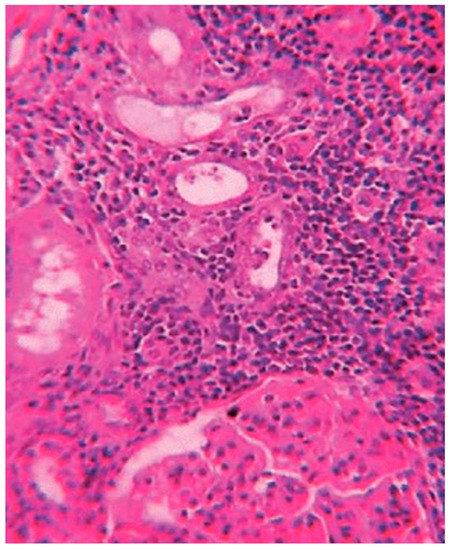

Histological exams showed a degenerative myocardiopathy and segmental vascular insufficiency, associated with myocardial micronecrosis foci. Lungs presented diffuse alveolar damage, with chronic interstitial pulmonary disease. Kidney showed necrotic degenerative changes of the tubules and glomeruli with interstitial nephritis (see Figure 2). The presence of the greenish liquid was confirmed in the stomach and in the small intestine, with both presenting mucosal inflammation and gastric necrotic areas (see Figure 3). Finally, there was mild fatty liver disease.

Figure 3. Mucosal inflammation and necrotic areas of the stomach.